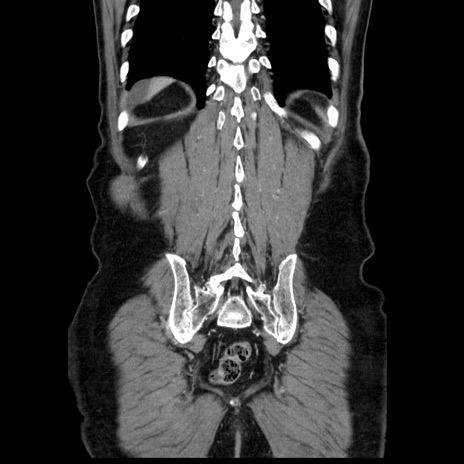

症例30(冠状断像)

【症例】80歳代男性

【主訴】臍周囲痛

【現病歴】約6時間前から臍下部痛が出現。次第に腹部膨隆・背部痛も生じてきたため来院。背部痛の場所は変化しない。

【身体所見】意識清明、BT 36.3℃、BP  131/87mmHg、P 87bpm、SpO2 100%(RA)、臍周囲自発痛・圧痛あり、反跳痛なし、自発痛部位に一致して板状硬あり、腹部膨隆、腸雑音減弱、CVA tenderness両側陰性。

【データ】WBC 19600、CRP 0.33